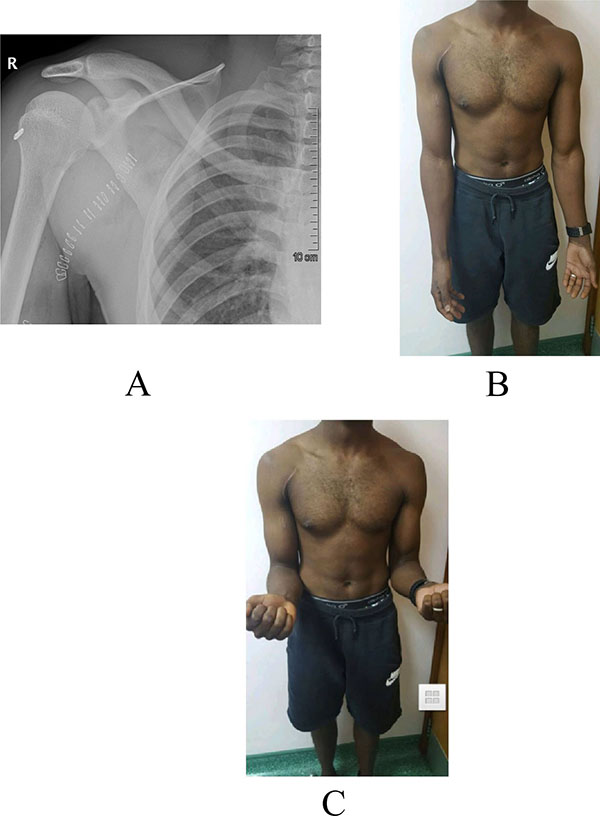

A 28 years old healthy man had a sudden jerk of his flexed right elbow to extension by the tension of the towrope as the boat accelerated away while involved in water skiing sports. He presented to the emergency department with severe pain in the anterior compartment of his right arm and a “Popeye” deformity, with clear rupture of the long head of the biceps (Figs. 1A, 1B). The plain radiographs of the left arm, elbow, and forearm did not reveal any fractures or dislocations. Magnetic resonance imaging showed complete proximal rupture of long head of biceps tendon.

By the end of one year, patient regained symmetrical muscle bulk, shape and contour of biceps compared to other side (Figs. 8B, 8C). There was no signs of dislodgement or loosening of the Endo Button on follow-up radiographs. He regained full muscle power in the biceps without any possible complications, such as humeral fracture, infection, or nerve injury, associated with this technique.